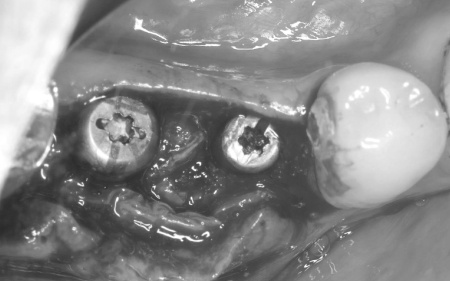

治療中